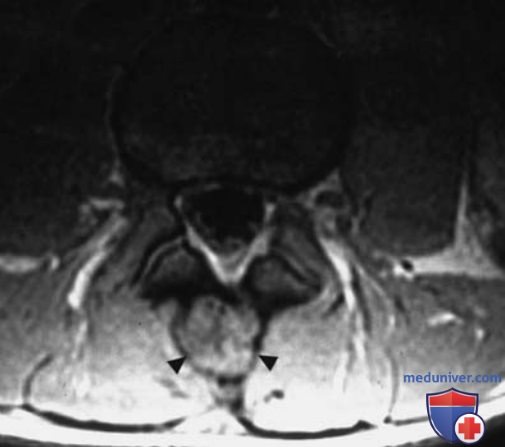

МРТ доброкачественных опухолей костей и опухолеподобных поражений

Рисунок 2. Остеобластома L4-позвонка. T1в-SE-изображение в аксиальной плоскости. Определяется патологическое образование размером примерно 2 см, с гетерогенным сигналом, окаймленное гипоинтенсивным кольцом. Поражение вызвало заметное вздутие остистого отростка позвонка (головки стрелок).